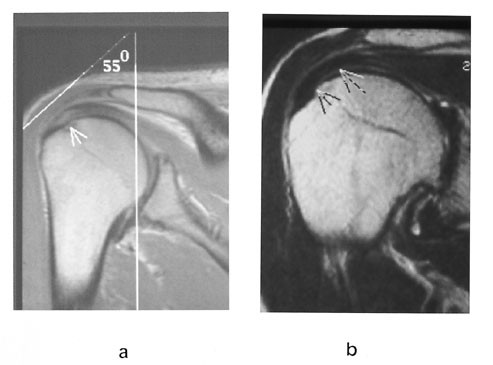

Rotatorcuffruptur er en samlingsbetegnelse på ruptur av senene til en eller flere av de fire rotatorcuffmusklene. Hyppigst forekommer ruptur av supraspinatussenen, fordi blodforsyningen til muskel-sene-overgangen er dårlig (fig 10). Diagnose av ruptur er den samme som for ligamenter ellers. Partielle rupturer fra undersiden kan være vanskelig å diagnostisere ved MR. MR-artrografi vil vise kontrastutsiving inn i senen fra undersiden. Trange forhold for m. supraspinatus og sene lar seg lett diagnostisere ved en skrå sagittal sekvens. Da får man fremstilt den akromio-klavikulære buen på en ideell måte. Det skal bemerkes at det er andre årsaker til såkalt innklemmingssyndrom enn trange forhold, som for eksempel periartikulære ganglier (fig 11).

Ved spørsmål om instabilitet eller residiverende luksasjoner, utføres en MR-artrografi. Man ser etter forandringer i labrum, fossa glenoidalis, kapsel med ligamenter og caput humeri. I tillegg til de vanlige projeksjonene utføres også en såkalt ABER (abduksjon ekstern rotasjon)-projeksjon (9) (fig 12). Pasienten ligger med armen rotert over hodet. Snittene legges parallelt med lengdeaksen av humerusdiafysen. De fremre strukturer blir dermed lagt i strekk og patologiske forhold blir synlige (fig 12).

Det finnes flere typer labrumvarianter som kan fremstå som patologiske, f.eks. sublabralt hull og Buford-kompleks (8). MR-artrografi vil kunne identifisere disse. Det er viktig ikke å overdiagnostisere. Pasienten bør slippe en unødvendig artroskopi.